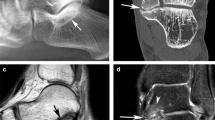

22-year-old male with an I-MP type coalition involving both middle and posterior facets. (A) The tarsal sinus (black arrow) can be seen. A significantly overgrown talus (white arrow) covers the calcaneus. The marginal cortical irregularity of the calcaneus is also noted. (B) The tarsal sinus cannot be seen and only the posterior facet is shown (white arrow). The two images (A, B) indicate that the coalition involved both the middle and posterior facets. A significantly overgrown talus (white arrow) covers the calcaneus. The marginal cortical irregularity of the calcaneus is also noted. (C) 3D reconstruction image shows that the overgrown talus covers the calcaneus like a shingle (oval) without the open of sinus tarsal

21-year-old man with an II-P type coalition involving the posterior facet only. (A) The tarsal sinus cannot be seen; both talus and calcaneus (white arrows) overgrow to adapt to each other. (B) 3D construction shows the open of sinus tarsal (black arrow); A significant coalition (oval) can be identified